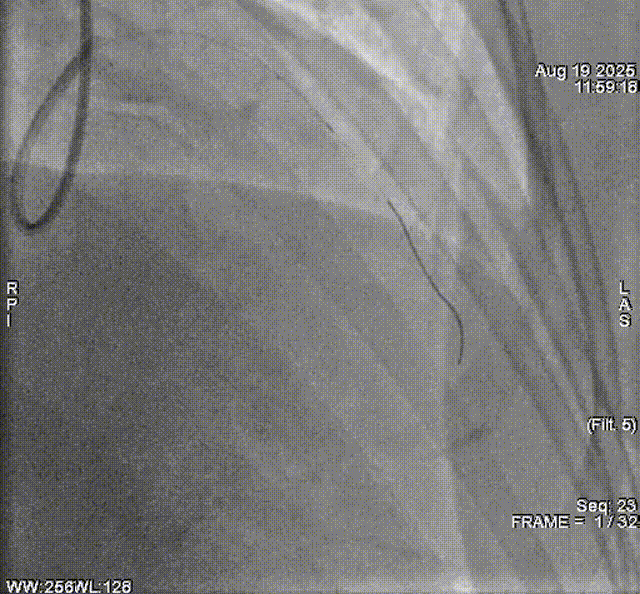

术后复查造影示前降支支架贴壁良好

撤出球囊导管,再次送入IVUS导管检测提示:前降支支架形态、贴壁均良好,无夹层、血栓及血肿。

术后复查IVUS